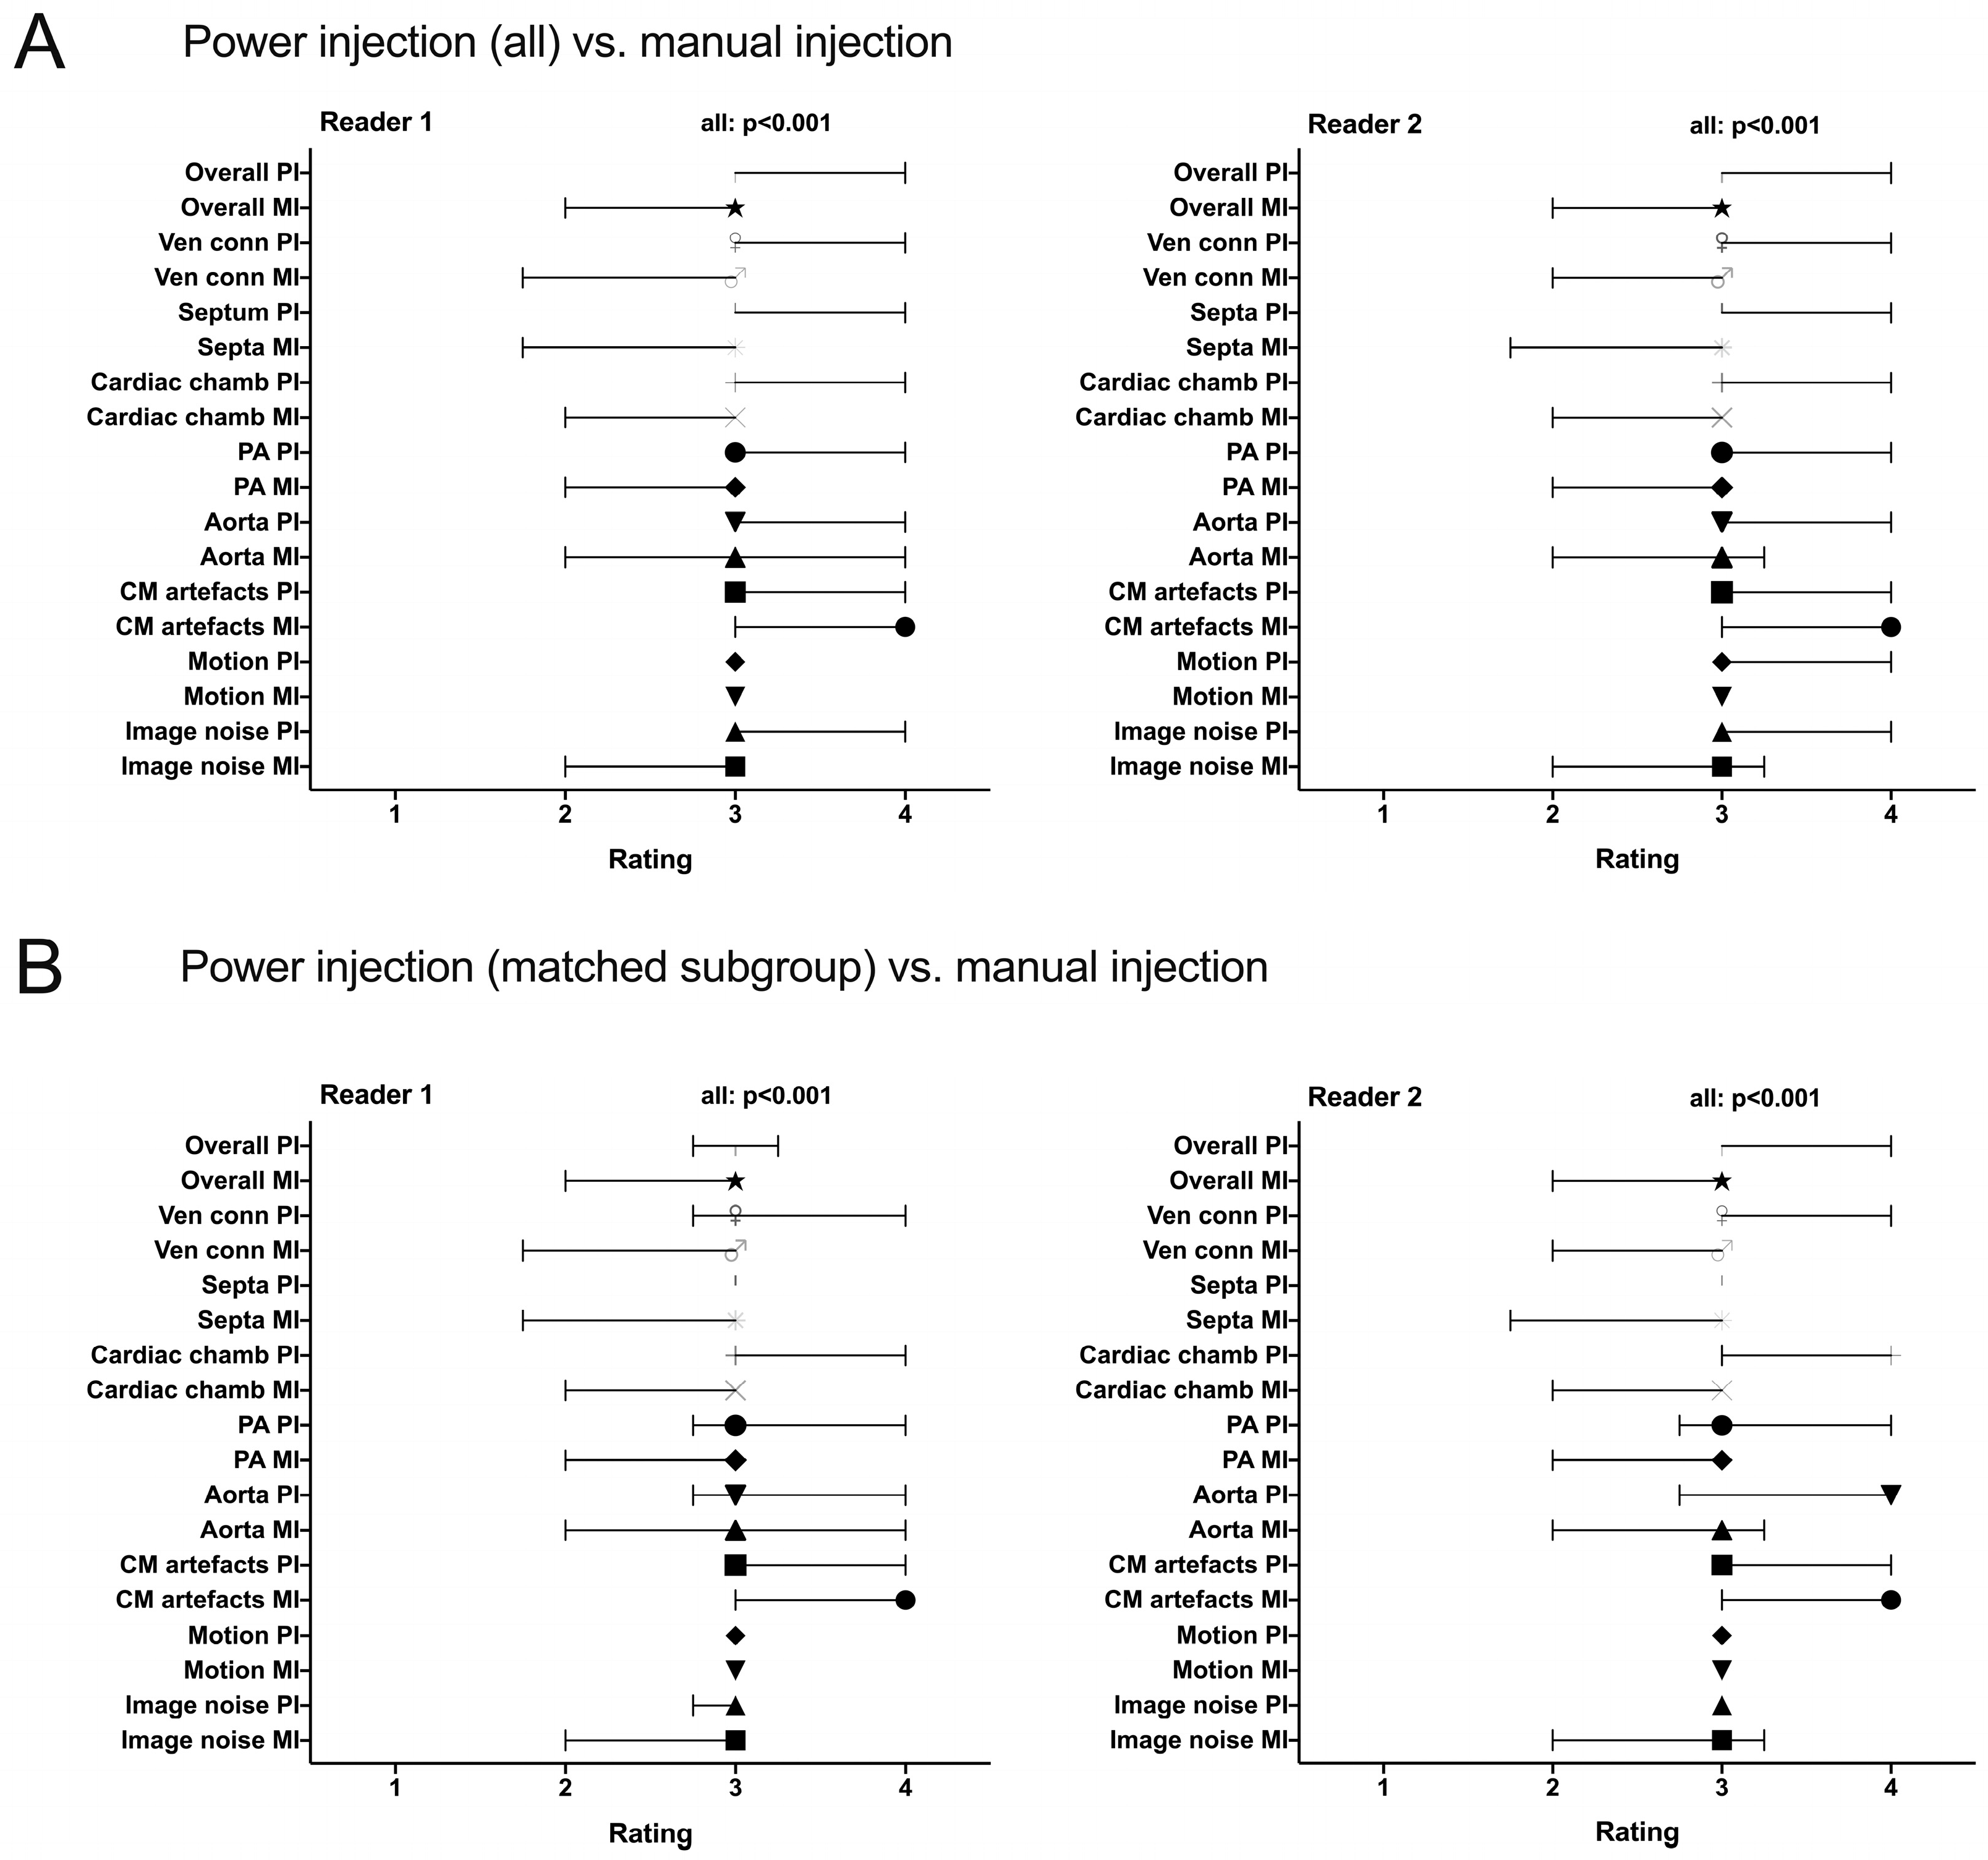

2.4. Assessment of Subjective Image Quality

3.3.2. Subjective Image Quality